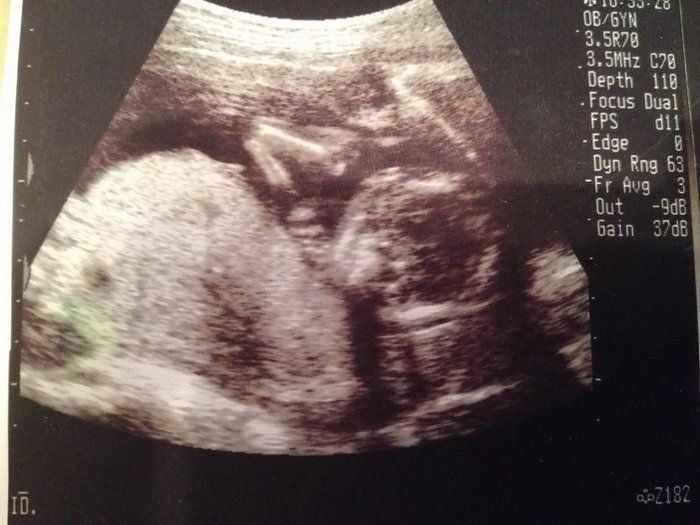

小吉さんの妊娠16週目のエコー写真

赤ちゃんの顔が正面からはっきり写っています。目鼻立ちも分かるので、赤ちゃんの顔を想像していたように思います。あごの近くにある2つの白丸は小さな両手です。